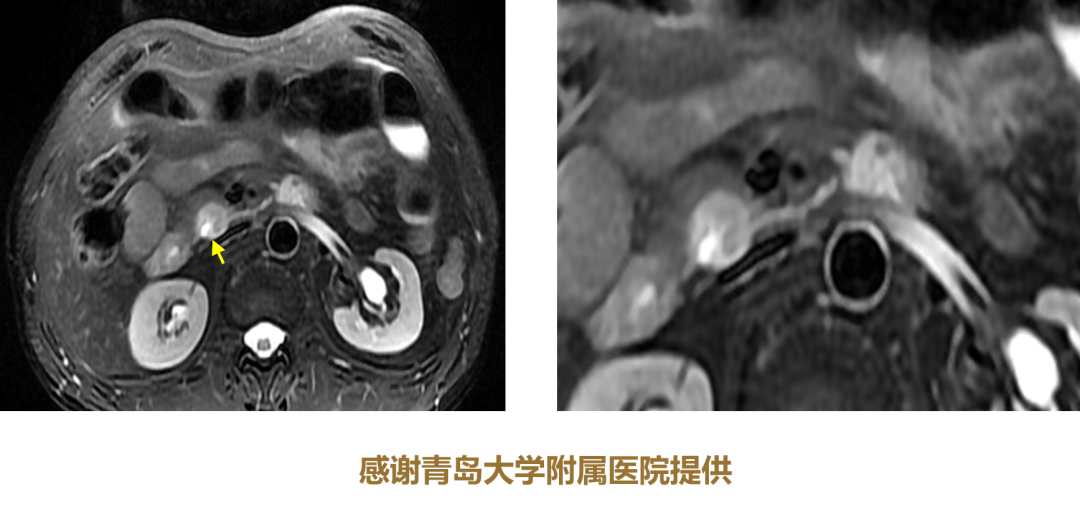

2. 胰管截断征

胰体癌造成的胰管截断,有助诊断。

图13 鉴别要点:无胰管扩张的花瓣征多为SCN;下游胰管扩张的花瓣征为IPMN

(图片来源:余日胜教授讲课使用)

7.葡萄征

SCN和导管内乳头状黏液肿瘤(IPMN)的鉴别要点为,无胰管扩张的花瓣征多为SCN,下游胰管扩张的花瓣征为IPMN。MRCP非常重要。

10.胰管鼠尾征

胰管轻度扩张且慢慢变细,为良性特征。慢性胰腺炎。

图15 胰管截断征与鼠尾征对比